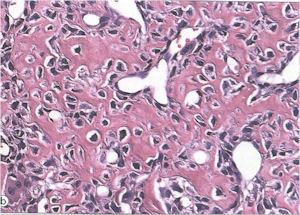

Microscopic Pathology

- Interlacing network of bone trabeculae in a loose fibrovascular stroma

- Prominent vessels

- Osteoblasts are plump, active, scattered mitotic figures

- Osteoblasts line up around periphery of trabeculae (Osteoblastic Rimming)

- Soft tissue component usually surrounded by shell of reactive bone or periosteum (Egg Shell Rim of Calcification)

- No cartilage production (as opposed to osteosarcomas that may contain areas of cartilage)